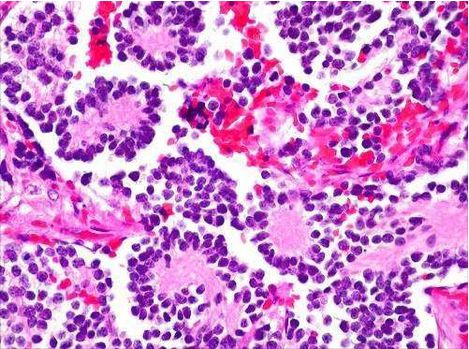

Which rosettes are seen in Neuroblastoma? _____